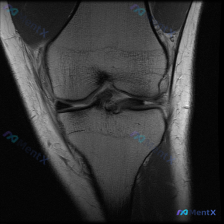

遇到一个挺典型的「临床-影像不匹配」的病例,整理出来和大家聊聊思路。 病例核心信息 问题:临床怀疑存在半月板异常,仅提供单张膝关节MRI-T2序列矢状位影像,请给出影像判断和分析。 影像所见整理 这张影像的情况是: 1. 骨结构:股骨远端、胫骨近端、髌骨皮质轮廓完整,骨髓信号均匀,没有骨折、骨挫伤、...

看到一个有意思的读片病例,整理一下资料和分析思路,跟大家分享一下。 病例基本信息 核心问题:患者主诉怀疑「半月板异常」,提供一张膝关节矢状位T2加权MRI图像,要求分析影像表现。 影像学读片结果 我们先逐结构捋一遍: 1. 图像质量:这是标准的矢状位T2加权图像,解剖结构清晰,对比度好,没有明显运动...

拿到这份病例和影像,先整理一下所有信息,再梳理思路: 一、核心临床问题 本次提出的核心疑问是:判断是否存在半月板异常 二、现有影像学发现(膝关节MRI T2序列冠状位单层面) 我先把所有客观发现整理出来: 1. 骨骼与关节软骨:股骨远端、胫骨近端骨皮质连续,无骨折;骨髓信号均匀,无明显水肿/硬化;关...

看到一份膝关节MRI的读片需求,核心问题是半月板异常,我整理了完整的分析思路,分享给大家。 病例影像基础信息 这是一张膝关节矢状位T2加权MRI,观察层面为膝关节外侧室,可显示股骨外侧髁、胫骨外侧平台、外侧半月板体部结构。 系统性影像学发现 1. 骨骼与关节软骨:股骨、胫骨骨皮质信号正常,骨髓无异常...

最近碰到一个有意思的读片病例,患者临床提示半月板异常,但提供的单张MRI并没有看到明确问题,整理一下完整的分析思路给大家参考。 一、病例核心信息 这是一份膝关节矢状位MRI扫描图像,临床问题是排查"半月板异常",我们先对影像做系统性评估: 1. 影像基本信息:这是T2/质子密度加权矢状位图像,清晰显...